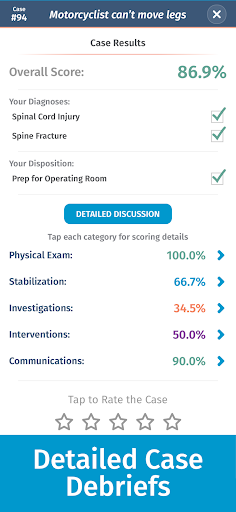

• Điểm số chi tiết và phân tích toàn bộ trường hợp - tìm hiểu điểm mạnh và điểm yếu của bạn

Các trường hợp có thể lặp lại vô hạn của Full Code đo lường các kỹ năng trong cả chẩn đoán và quản lý, cho phép bạn học hỏi từ những sai lầm của mình trong một môi trường không có rủi ro. Xây dựng năng lực để bạn có thể đối mặt với các trường hợp thực tế phức tạp một cách tự tin.